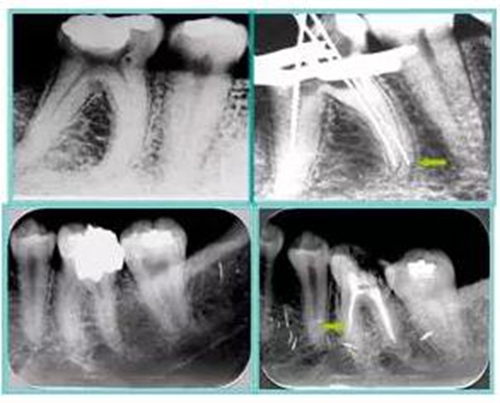

6. 術(shù)后 X 線片

術(shù)后 X 線片用來評(píng)定根管充填 長(zhǎng)度、致密度(管壁清晰、側(cè)枝)等指標(biāo)。

15.jpg

左圖為根管充填術(shù)后 X 線片。圖中可見,根管充填較好。右下圖有白色小點(diǎn),為側(cè)方加壓導(dǎo)致糊劑擠出所致,表明根管充填比較致密。

致密、恰到好處的充填可去除干凈根管里感染灶,機(jī)體逐漸恢復(fù)。

16.jpg

多根牙時(shí)候需進(jìn)行偏移投照,正位投照無法說明具體哪根牙根管充填效果。